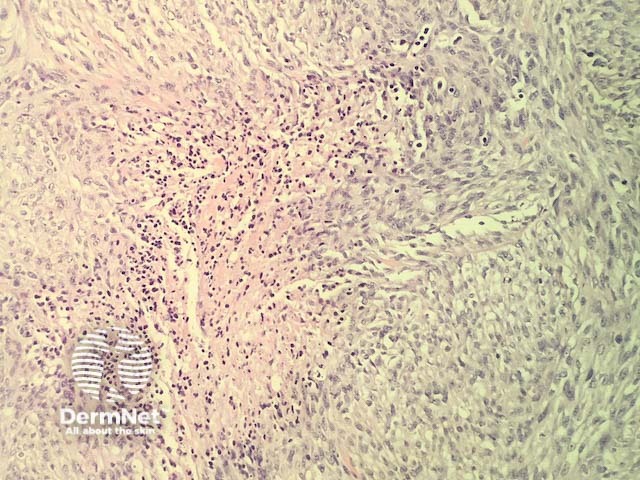

In mesothelioma, histopathology shows a diverse range of patterns: epithelioid, sarcomatous and biphasic (mixed). The majority of cases show a mixed pattern of epithelioid and spindled cells. In each of these subtypes the cells show marked nuclear atypia and invasion into surrounding structures. Metastasis to the skin usually shows a dermal tumour, often with overlying ulceration (figure 1). Higher power examination shows malignant cells with a variety of cell shapes ranging from tubulopapillary, spindled, clear cell, and small cell types. The example illustrated here is predominantly sarcomatous with a preponderance of spindled cells (figures 2-5). There are zones of necrosis (figures 3-5).

Figure 5